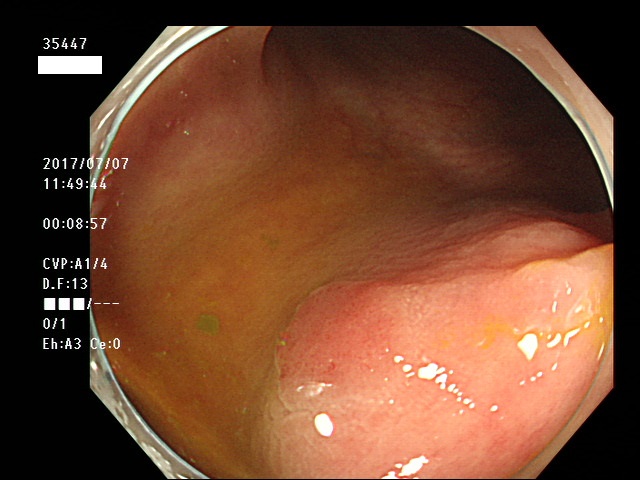

上記100名より抽出した平坦・陥凹型腺腫・SSAP(=癌化の危険が高いが見落としやすい病変)の内視鏡写真

35403 35404 35405 35409 35410 35412 35413 35414 35416 35417 35418 35419 35420 35421 35426 35429 35430 35433 35434 35435 35438 35439 35440 35444 35445 35447 35449 35450 35451 35452 35453 35454 35458 35460 35463 35464 35466 35468 35469 35470 35472 35473 35478 35479 35481 35483 35485 35489 35490 35491 35492 35493 35498 ・・・・・の54名